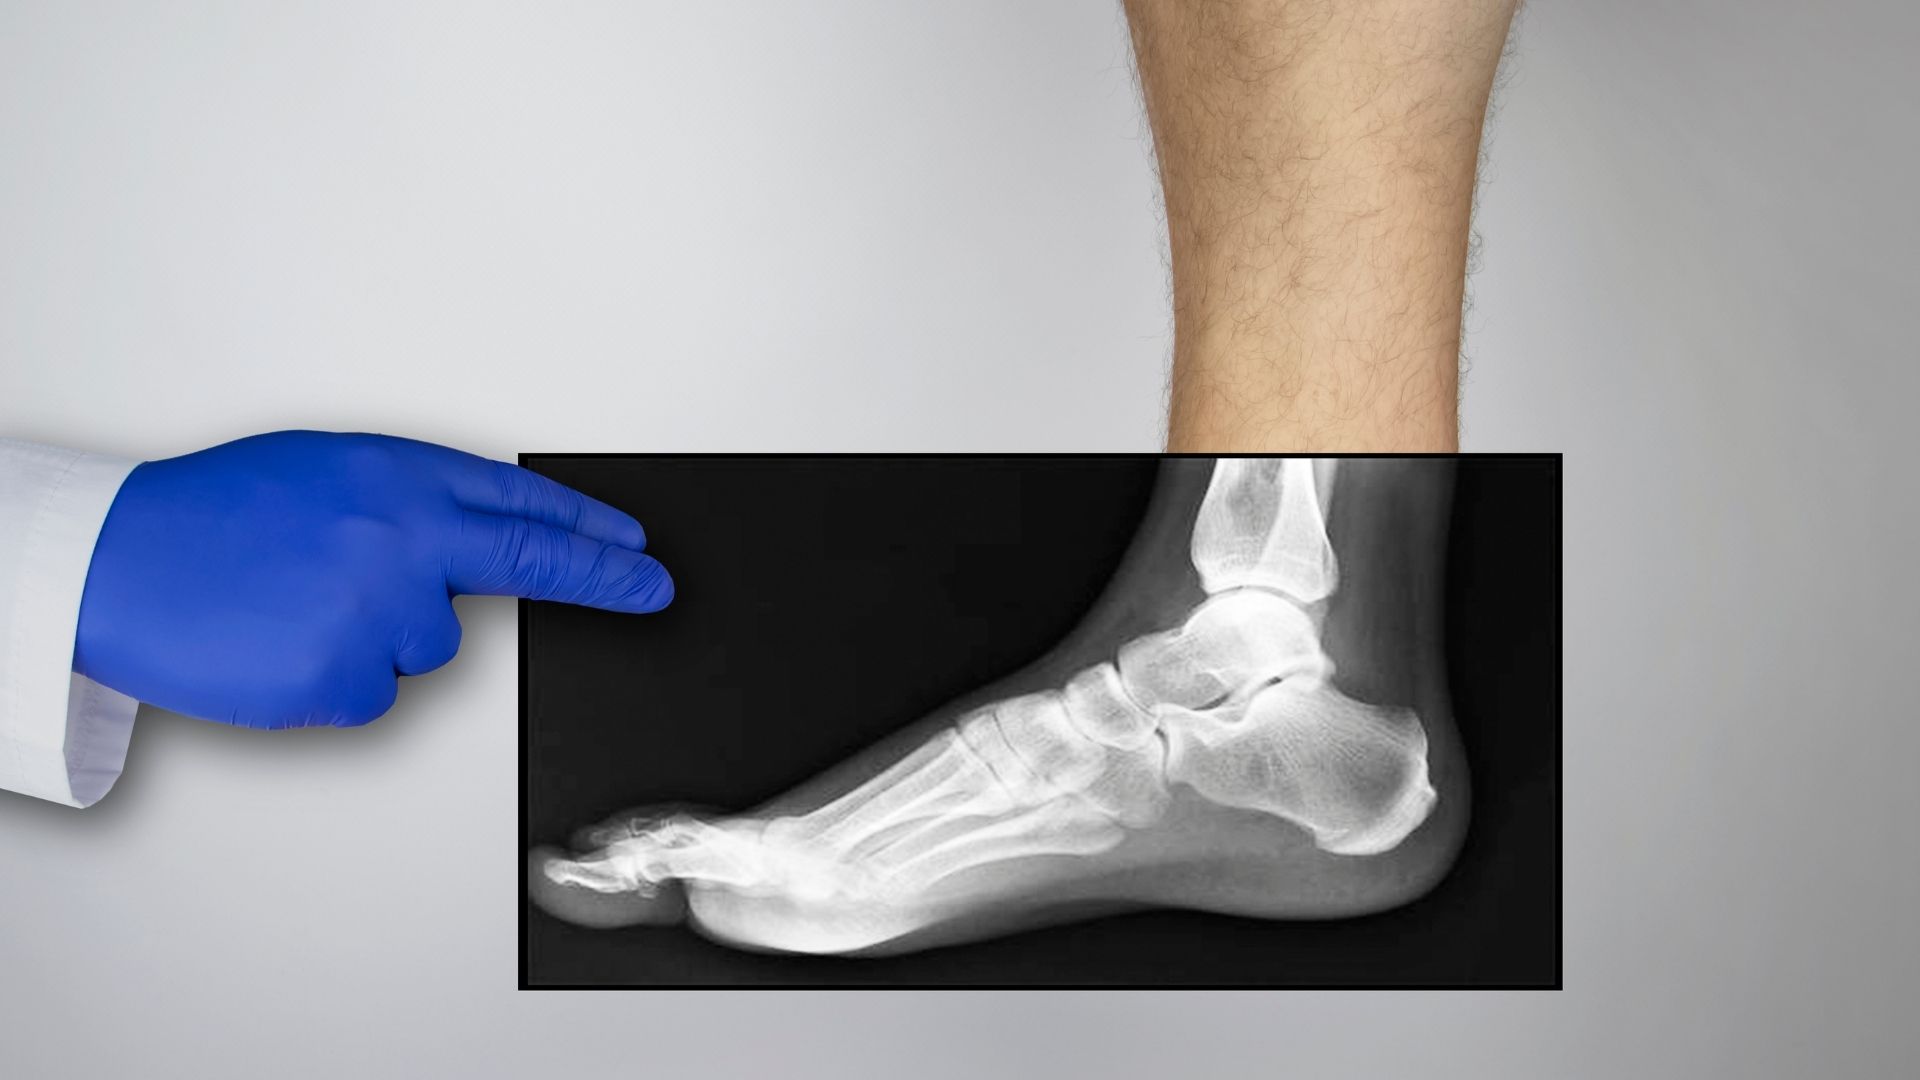

Chụp X-quang chân là kỹ thuật chẩn đoán hình ảnh sử dụng tia X để ghi lại hình ảnh cấu trúc xương và các khớp ở vùng chân. Thông qua hình ảnh thu được, bác sĩ có thể quan sát được tình trạng xương, phát hiện những bất thường như gãy xương, nứt, lệch trục hoặc các dấu hiệu tổn thương khác.

Điểm mạnh của kỹ thuật này nằm ở khả năng cung cấp hình ảnh rõ ràng về cấu trúc xương trong thời gian ngắn. Nhờ đó, bác sĩ có cơ sở để đưa ra chẩn đoán ban đầu và định hướng điều trị phù hợp. Với những trường hợp nghi ngờ tổn thương xương, X-quang thường là bước thăm dò đầu tiên trước khi cân nhắc các phương pháp chẩn đoán chuyên sâu hơn.

Tùy vào vị trí tổn thương và mục đích chẩn đoán, bác sĩ có thể chỉ định chụp X-quang chân ở một hoặc nhiều tư thế khác nhau. Tư thế chụp thẳng giúp đánh giá tổng quan trục xương và cấu trúc khớp. Trong khi đó, tư thế chụp nghiêng hỗ trợ quan sát rõ hơn các khe khớp hoặc những tổn thương khó nhận thấy ở tư thế thẳng.